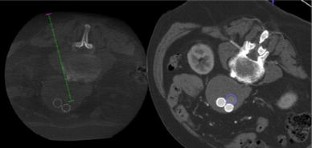

Eight patients with T2EL were treated with DPSI using CBCT as imaging guidance. Anatomical landmarks on unenhanced CBCT were used for referencing T2EL location in the first five patients, while FI between unenhanced CBCT and pre-procedural computed tomography angiography (CTA) was used in the remaining three patients. Embolization was performed with thrombin, glue, and ethylene–vinyl alcohol copolymer. Technical and clinical success, iodinated contrast utilization, procedural time, fluoroscopy time, and mean radiation dose were registered.

Fig. 1

Fig. 2